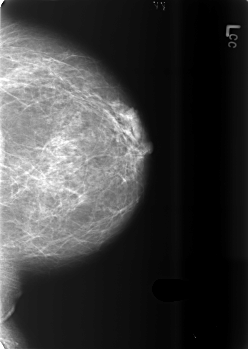

B_3432_1.LEFT_CC

LEFT_CC LINES 5584 PIXELS_PER_LINE 3960 BITS_PER_PIXEL 12 RESOLUTION 50 NON_OVERLAY